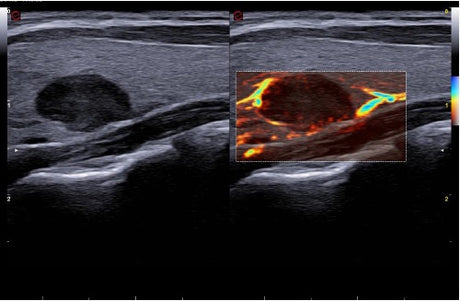

La qualité d’image est au cœur de la philosophie Esaote. Grâce à ses sondes de dernière génération et à son traitement du signal avancé, la marque permet une visualisation fine des structures anatomiques, même les plus profondes. Leurs échographes intègrent des écrans tactiles haute résolution, une interface claire et une connectivité complète, favorisant un flux de travail rapide et efficace.

Les échographes Esaote offrent une restitution d’image d’une grande précision, permettant un diagnostic fiable dans toutes les spécialités. Le traitement numérique optimise le contraste et la netteté, réduisant les artefacts et améliorant la détection des tissus pathologiques. Ces performances sont particulièrement appréciées en gynécologie, où la lisibilité des structures pelviennes ou obstétricales est déterminante.